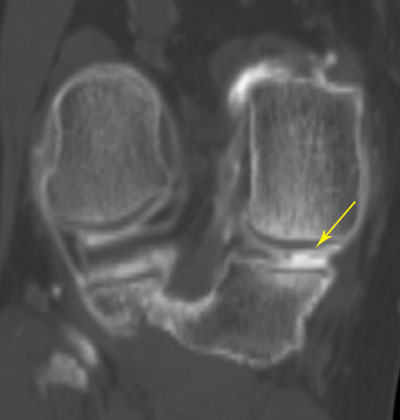

Genou

Chondropathie fémorale (atteinte du cartilage) Fissure du ménisque interne

(flèche du haut)

Kyste méniscal (flèche du bas)